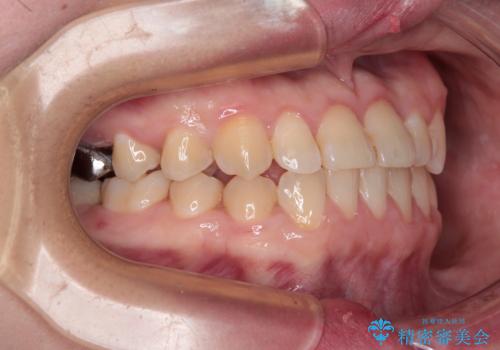

このような咬み合わせの方の多くは、舌の突出癖が強い傾向にあり、反対咬合改善後に開咬となってしまい、なかなか治療が終わらないことがあります。

こちらの患者様は、舌のトレーニングを治療開始前から徹底的に実践していただき、僅か8ヶ月という短期間で治療を終えることができました。